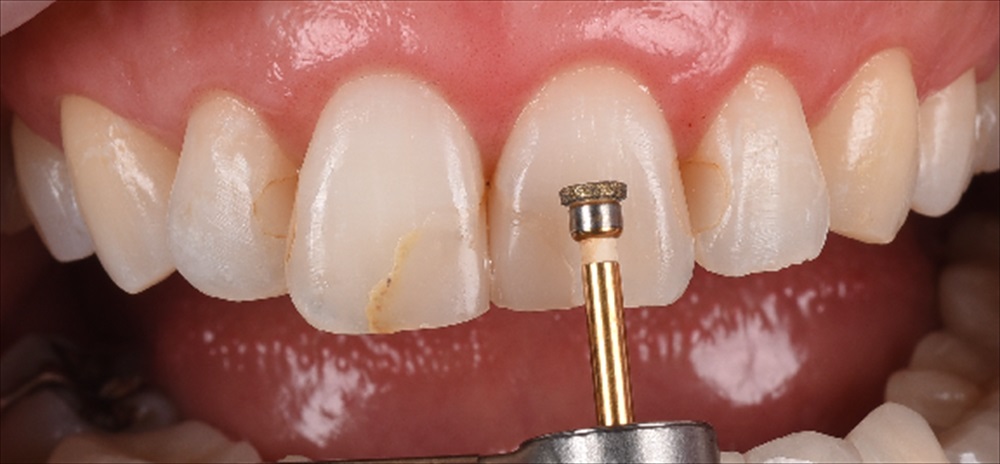

ここから歯をなるべく削らない作戦を技工士の間中とたてガイドを作成

見て頂くと分かると思いますが、前歯2本のみ0.7削り他はノンプレップ(削らない)です。

形成量はこの感じ。